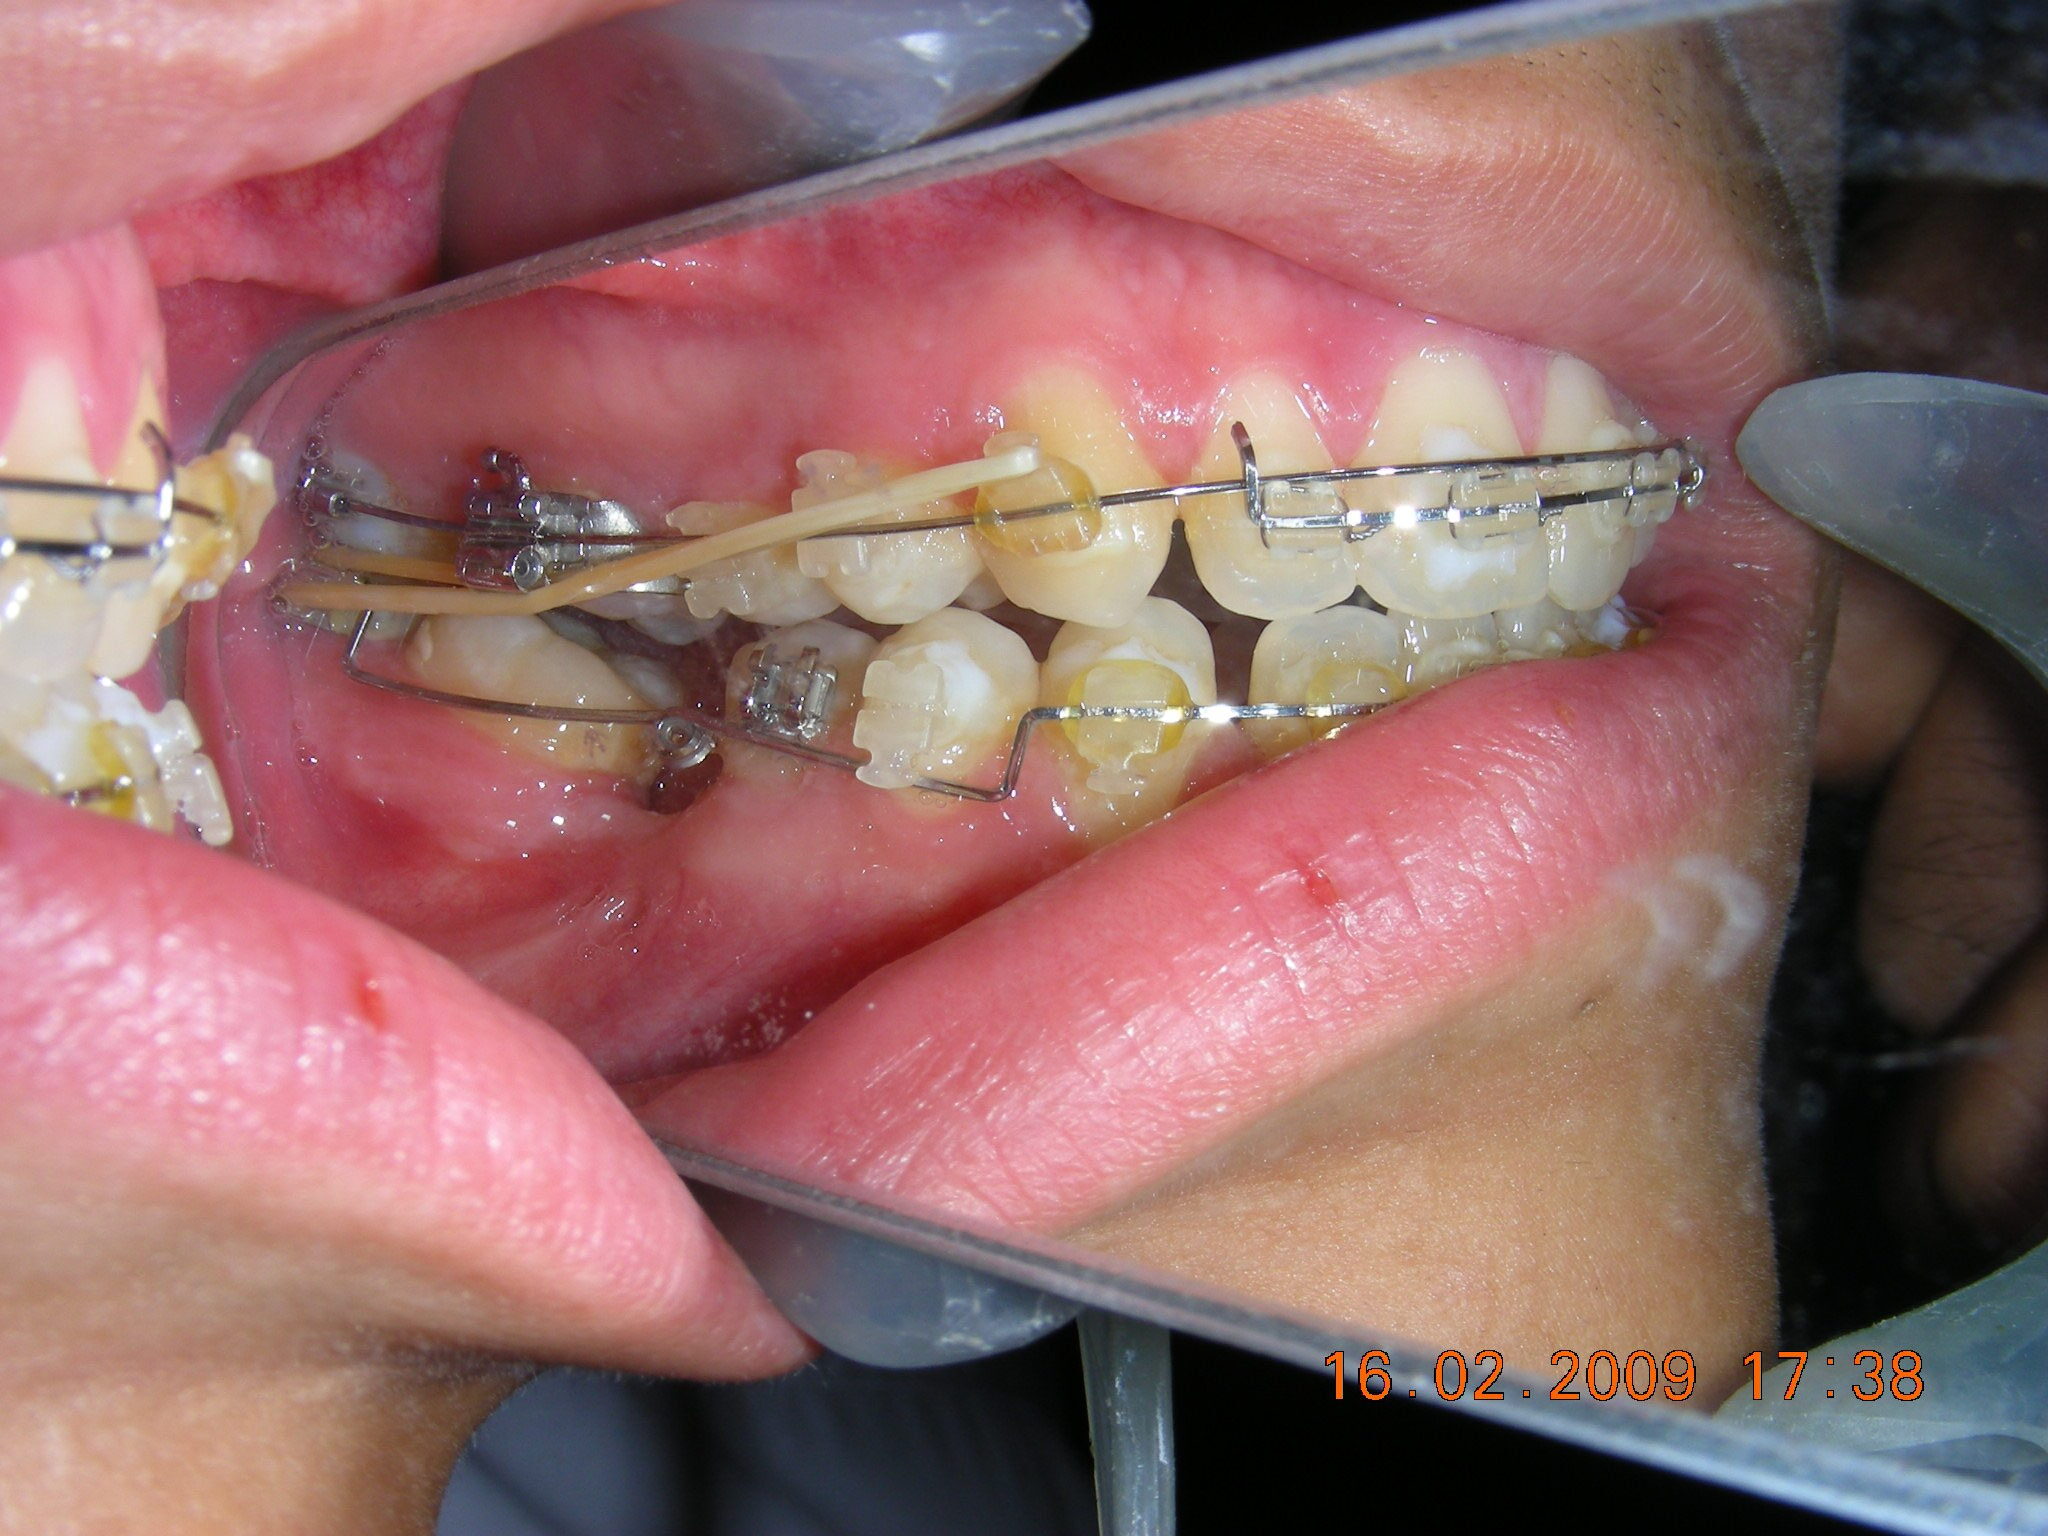

Was installed a Hyrax-type 10mm palatal expander of the Brazilian trademark Morelli® , modified by the author to be adapted to receive TADs microscrews, in order to initiate maxillary disjunction with MARPE (Mini-implant Assisted Rapid Palatal Expansion), TADS was installed with skeletal anchorage placed bilaterally having as references the roots of the maxillary canines and first premolars. Prior to insertion, local infiltrative anesthesia was administered using 2% lidocaine hydrochloride with 1:100,000 epinephrine. A total dose of approximately 0,8 mL per side (cortical infiltration technique). The TADs were inserted under aseptic conditions using a manual driver. Microscrew Evolution 1,6 Ø x 10 mm from the Argentine brand Odontit® . The Hyrax expander was then fitted and activated after 48 hrs .

Protocol of one activation per day was followed for a period of three weeks where the first clinical and radiographic evaluation was performed, showing clear signs of skeletal expansion, including the presence of a midline diastema. One more week of activations was added with a total of 28. The patient reported moderate headache during the first week of activation.

Having successfully achieved the expansion, we proceed to the intrusion of the posterior superior sectors, modifying the Hyrax by adding anchoring hooks at the buccal level of the first premolars. Using the Hyrax as anchorage, we sought a parallel intrusion. This could be replaced by a palatal bar. TADs were installed bilaterally at the mesial level of the first molars, inserting them as parallel as possible to the roots.

Simultaneously we begin with the alignment of the lower arch ,Simultaneously we began with the alignment of the lower arch with Roth prescription ceramic braces .022 . Henry Schein®